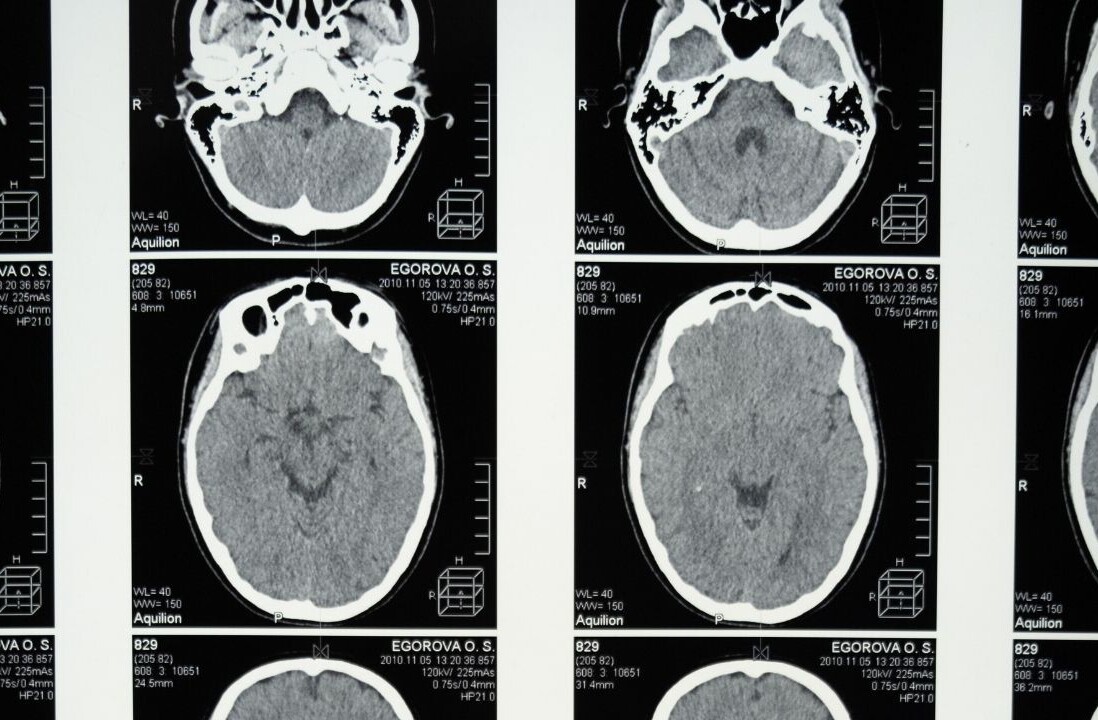

The brain’s hippocampus is a critical brain region for learning and memory, and is particularly vulnerable to such insults. Studies in humans have shown that inflammation can adversely affect brain systems linked to motivation and mental agility.

There is also evidence of chronic stress effects on hormones in the brain, including cortisol and corticotropin releasing factor (CRF). High, prolonged levels of cortisol have been associated with mood disorders as well as shrinkage of the hippocampus. It can also cause many physical problems, including irregular menstrual cycles.

There are many reasons for this, and they can be linked to changes in the brain. The reduced hippocampus that a persistent exposure to stress hormones and ongoing inflammation can cause is more commonly seen in depressed patients than in healthy people.